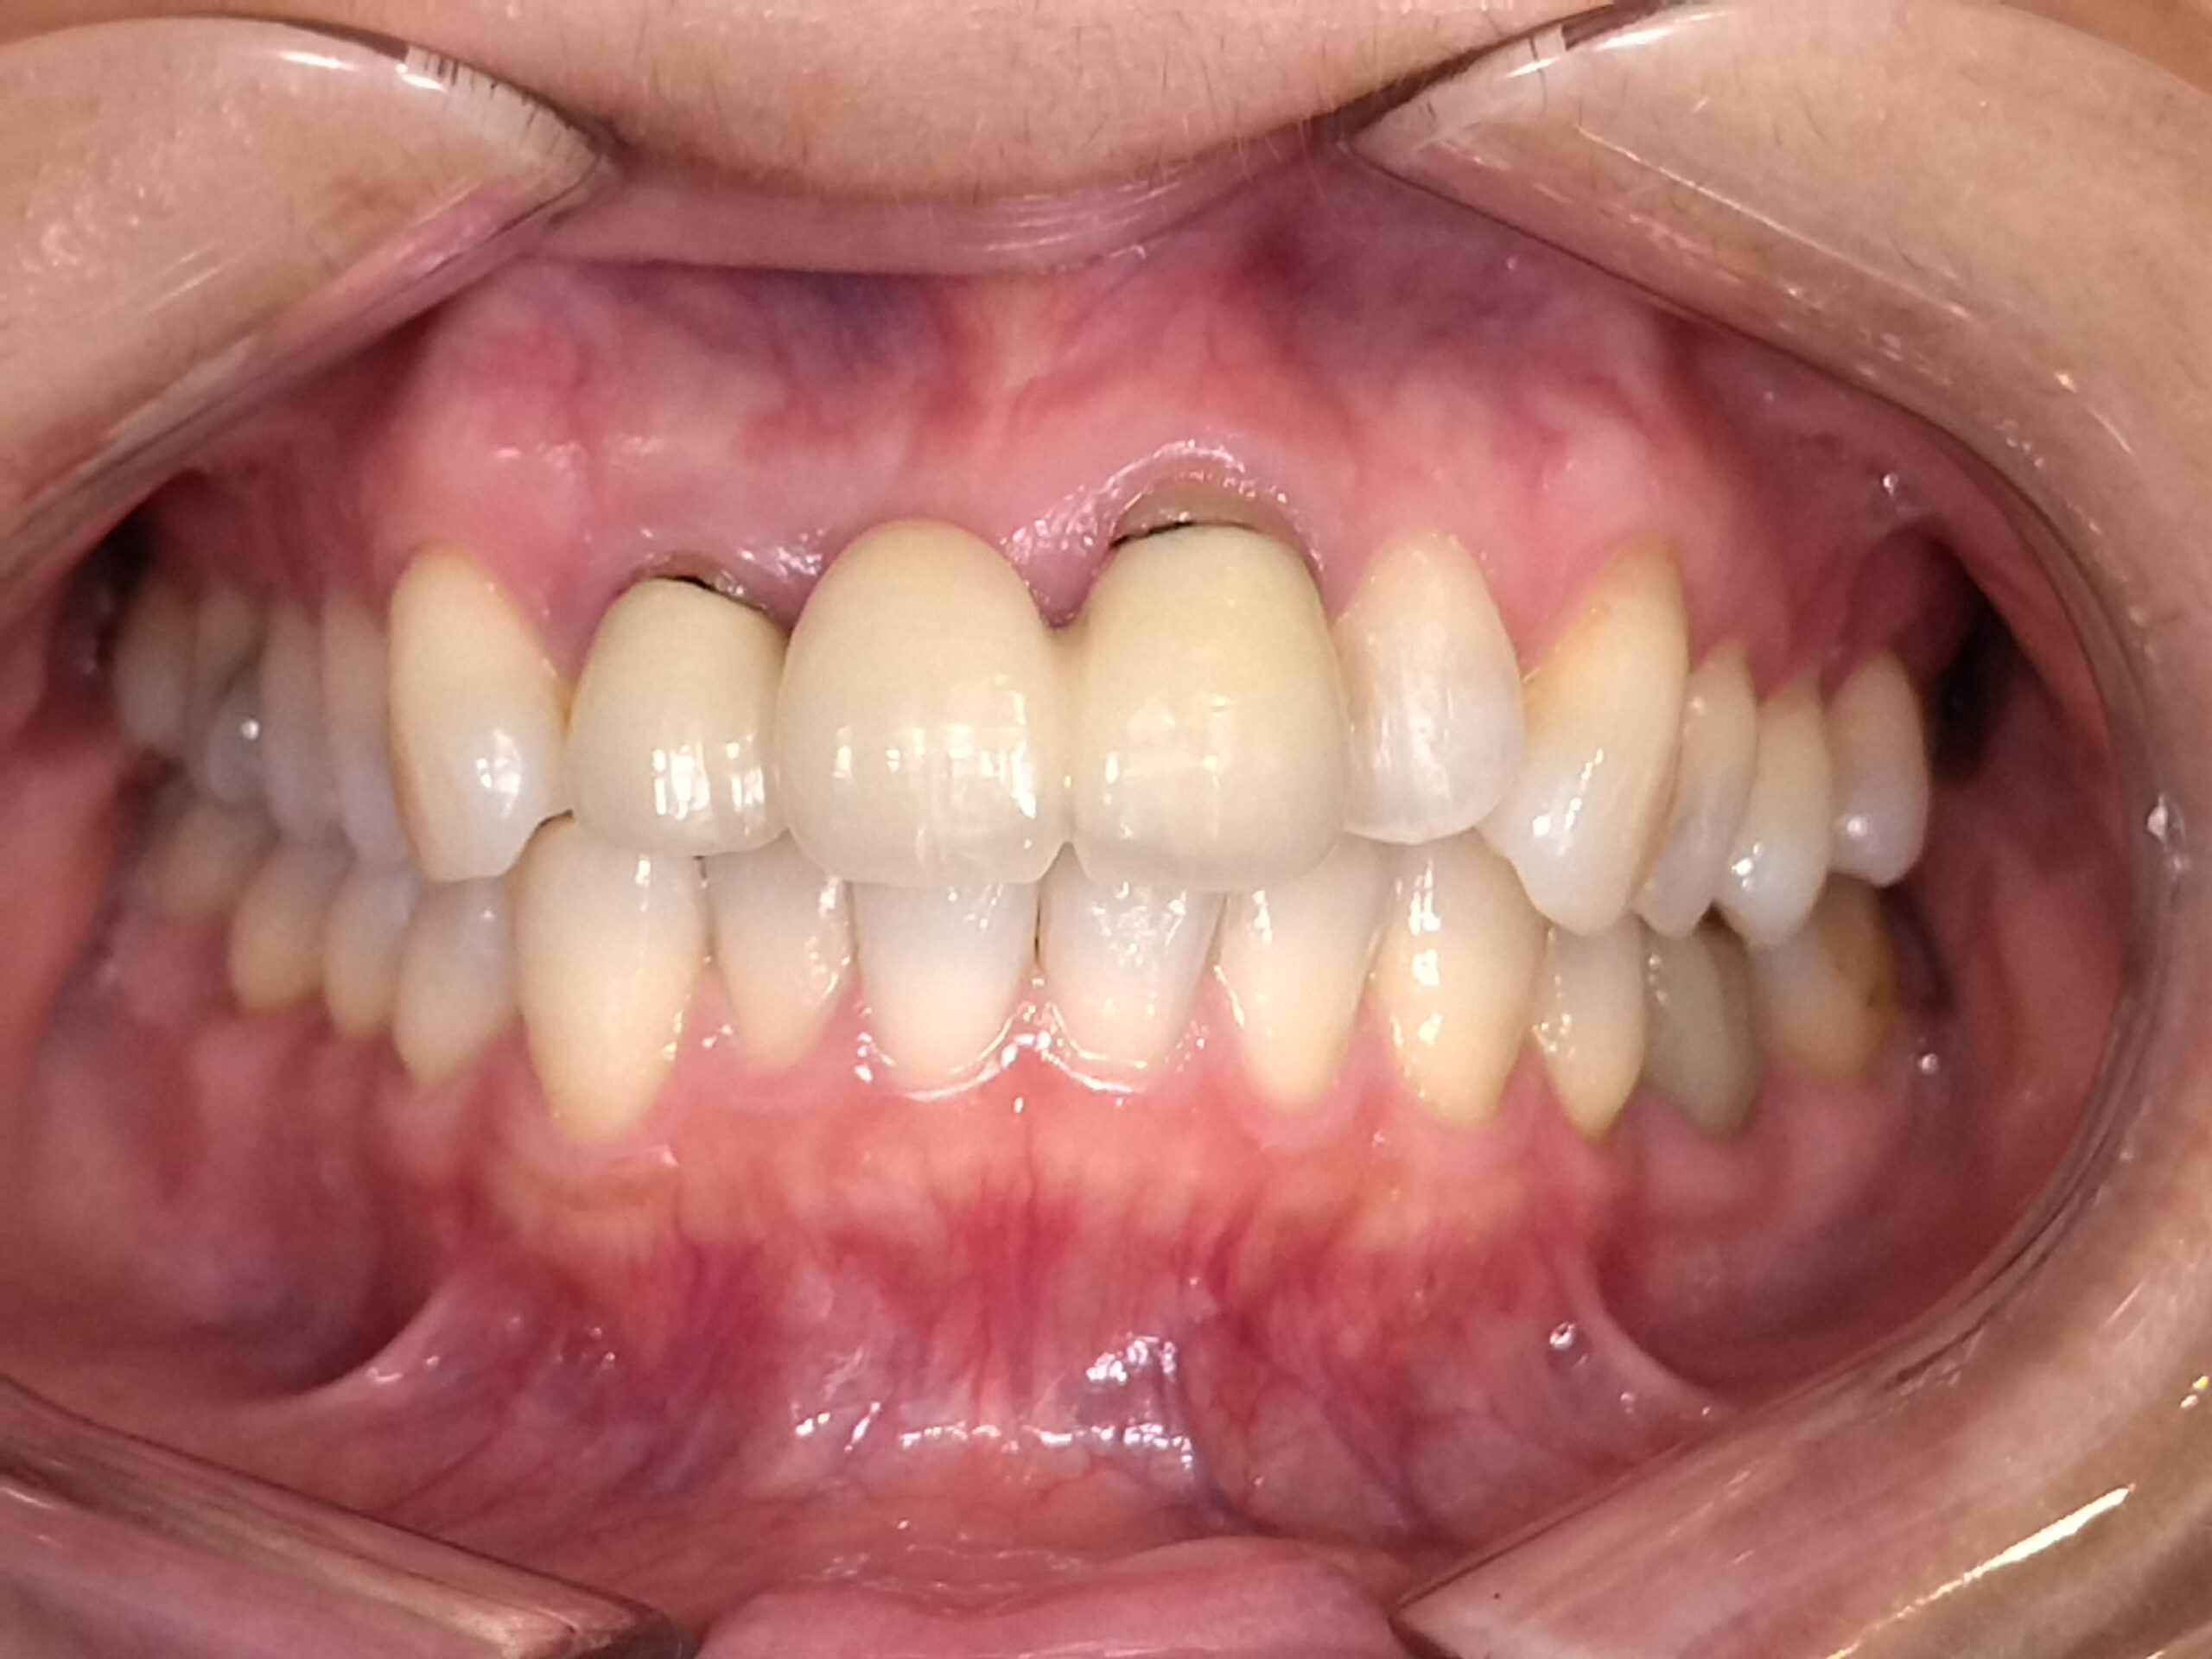

現在では、金属を使わないオールセラミック治療が主流となっており、自然な見た目を再現することができます。

• ジルコニアクラウンやe.maxクラウン

白く透明感のある素材で、金属を使わないため歯ぐきが黒く見える心配がありません。